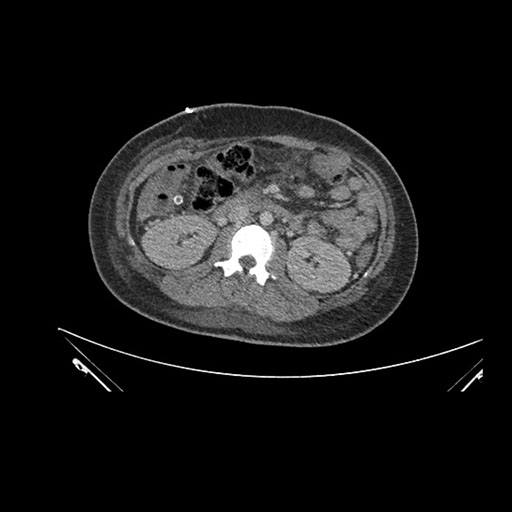

Axial Arterial

Axial Venous